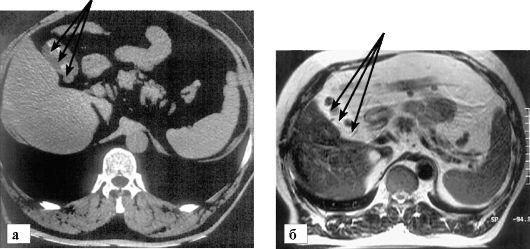

Компьютерная томография (КТ) позволяет получить полное представление о всей брюшной полости и тазу за один сеанс. При подозрении на острый холецистит КТ выявляет осложнения, которые могут быть незамечены при ультразвуковом исследовании. Четко видна утолщенная, воспаленная стенка желчного пузыря. Перихолецистическая жидкость и жировые отложения вокруг желчного пузыря указывают на воспаление.